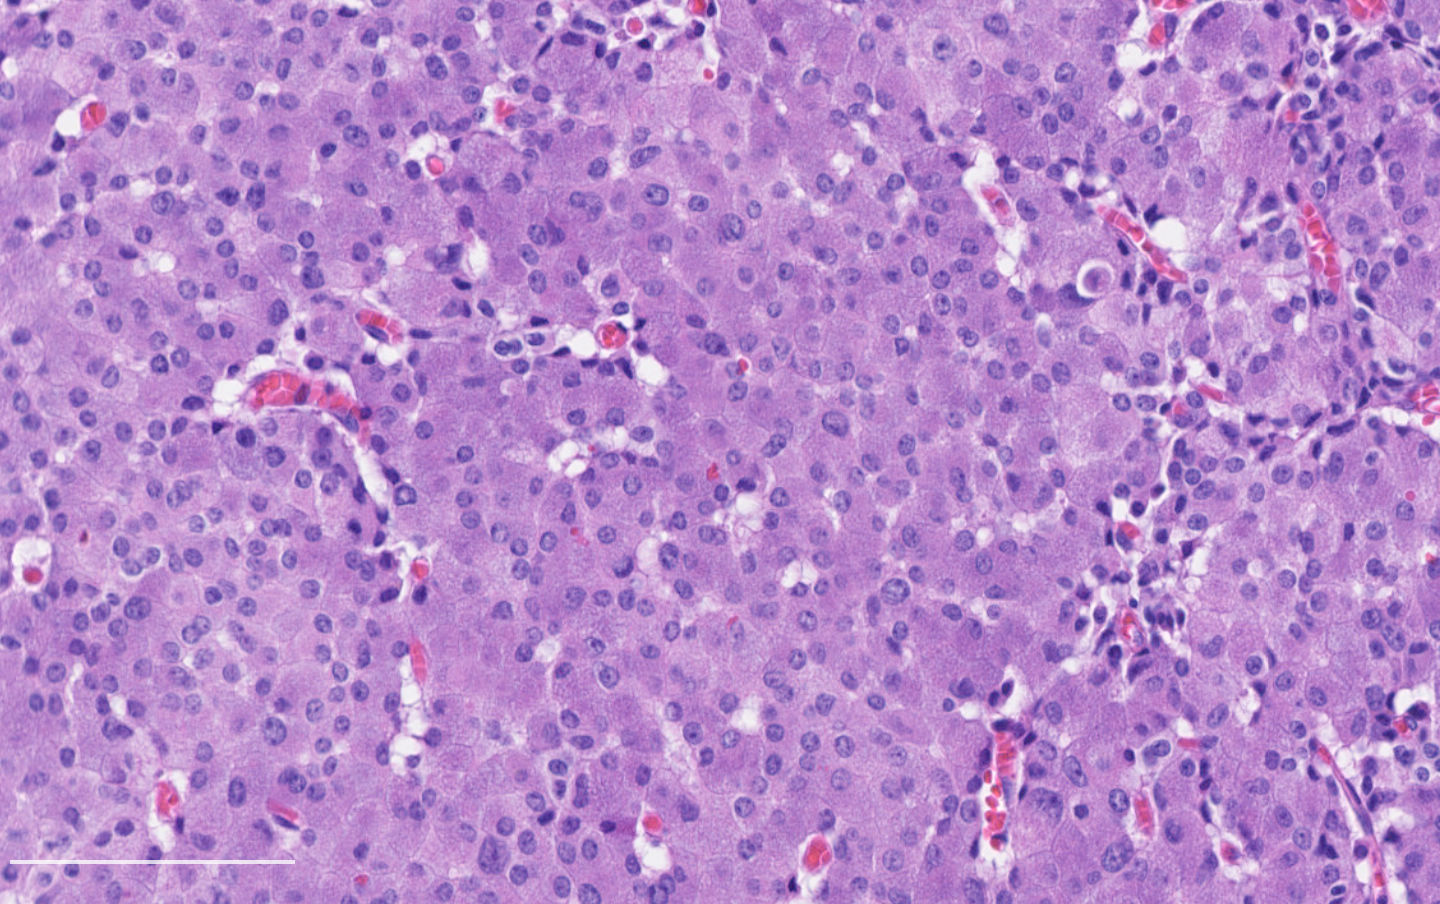

- Diagnostic criteria:

- Neuroendocrine morphology with 2 - 10 mitoses per 2 mm² or presence of necrosis

- Necrosis can be in large zones but is usually punctate

- Neuroendocrine histologic patterns similar to typical carcinoids: organoid, trabecular, rosette formation, papillary, pseudoglandular, follicular

- Tumor cells are as typical carcinoid: uniform with a polygonal shape, round to oval nuclei with salt and pepper chromatin and inconspicuous nucleoli, along with moderate to abundant eosinophilic cytoplasm

Contributed by Philippe Joubert, M.D., Ph.D.